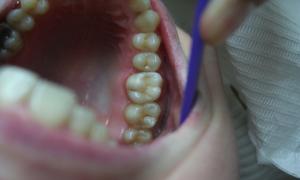

Chrup s amalgámovými výplňami

Výmena amalgámových výplní fotokompozitnými plombami s estetickým a anatomickým tvarom zubu